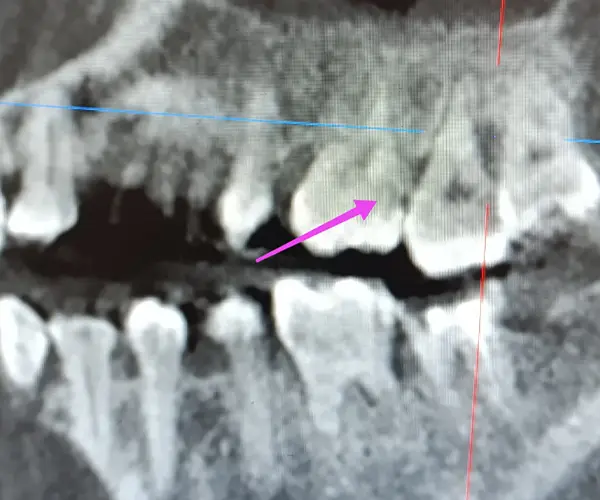

По результатам КЛКТ у пациента был выявлен дефект твердых тканей на дистальной поверхности зуба 2.6. Основной вызов — восстановить анатомию зуба, сохранив плотный апроксимальный контакт и обеспечив идеальную адаптацию композита к тканям зуба.